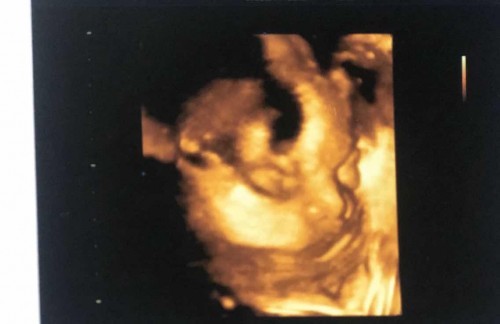

ลูกสาว34วีคแล้ว

34วีคแล้วจ้า น้ำหนักตอนนี้ได้2.2โลแล้ว คุณหมอบอกว่าหนูเริ่มเอาหัวหมุดลงแล้วน๊า ท้องแข็งบ่อยมาก ๆๆๆ แต่ตอนนี้แม่เลือดจาง31% แม่แอบกังวลมากๆ เพราะคุณหมอบอกว่าแม่มีสิทธิ์ตกเลือดหลังคลอดได้😢